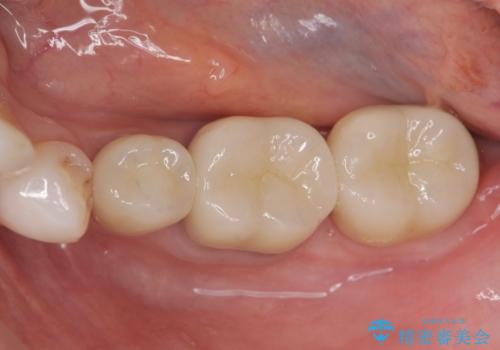

- 違和感や疼きのある左側小臼歯に加え全体的にクラウンや詰め物のやりかえを希望され来院されました。

治療後に再発した虫歯や根管再治療に加え、穴の空き症状のある上顎左側小臼歯は抜去を行いインプラントによる機能回復治療を計画します。

X線写真検査ではわからない虫歯も外してみると再発していることがあります。虫歯を丁寧に取り除き、再発を防ぐべく精密なクラウンの作製を行うことが長期的な予後につながります。